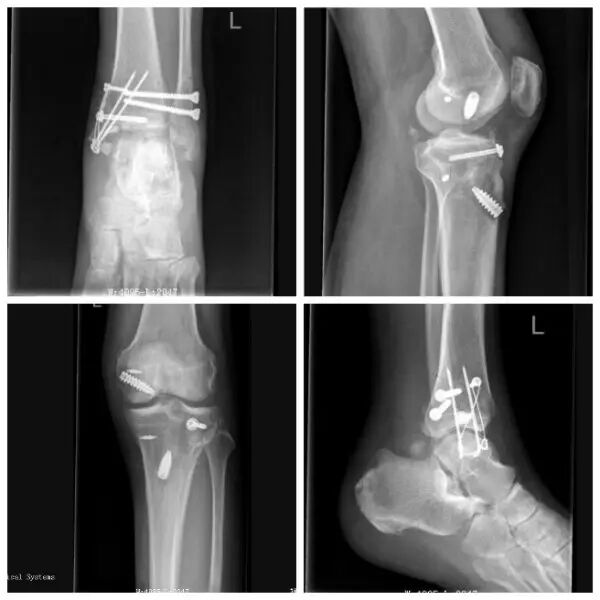

小腿植皮全部活了!随着打开绷带的一瞬,骨二科马中兴主任内心充满成功的喜悦,患者老梁也流下了感激的泪水。历经四次手术,四十多个日日夜夜的精心治疗,从急诊保肢到功能重建,再到创面修复,这例复杂严重肢体创伤患者的救治终获成功,证明了我院骨科团队是一支敢于担当勇于挑战的队伍。

随即我院启动急救绿色通道,老梁直接被送入急诊手术室,经过一个多小时的奋力手术,血流终于再次灌通老梁的左脚,老梁的脚保住了!之后骨二科团队又择期分别为老梁施行了关节镜下膝关节韧带重建术,骨折内固定术和植皮术。针对老梁制定的分期治疗计划同时也得到了南京市一院专家的肯定和支持。这是我院骨科采用先进的损伤控制理念和关节镜下微创修复技术治疗复杂严重创伤的一次重要实践。